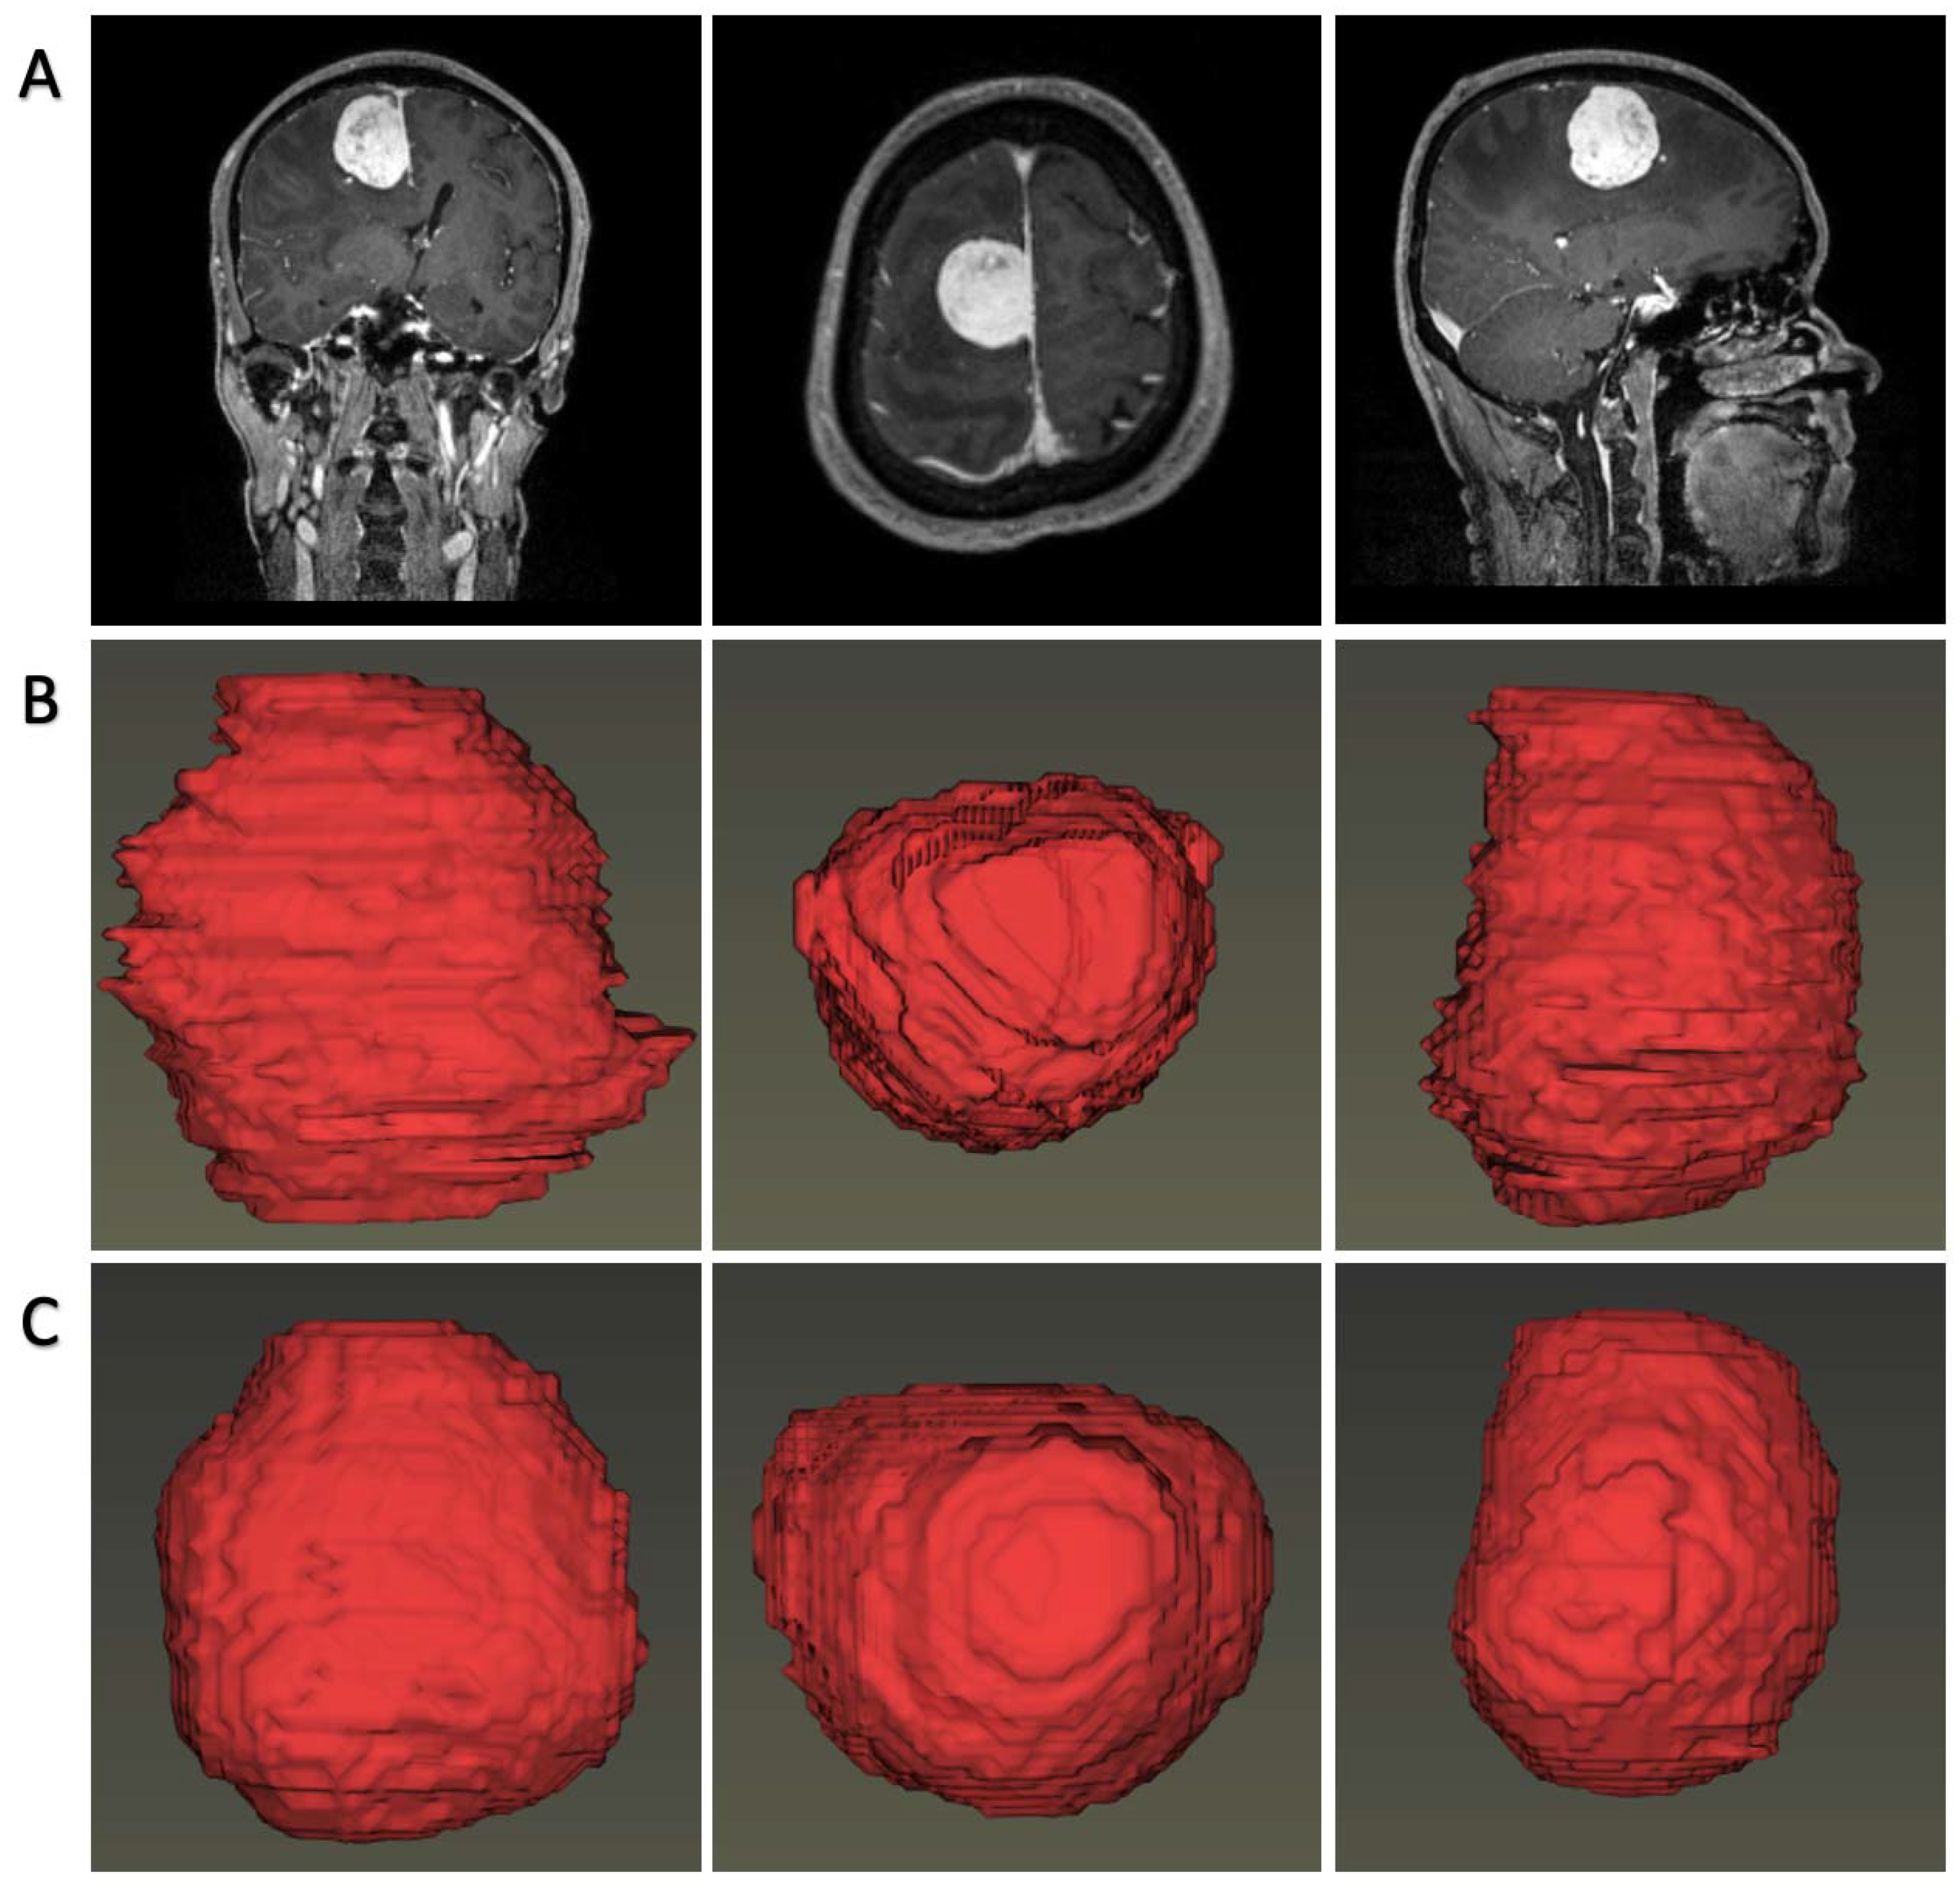

In most cases, both 2D-U-Net and 3D-U-Net can accurately segment tumors on axial images. Figure 2 represents the predicted section examples from the models’ tumor predictions in comparison with the manual segmentations. Specifically, the performances for the 2D-U-net network in the validation groups were: dice = 0.920 ± 0.009, Jaccard = 0.851 ± 0.016, TPR = 0.999 ± 000, FPR = 0.000 ± 0.000, and calculation time = 70 ms/image. Additionally, for 3D-U-net, the results were: dice = 0.873 ± 0.020, Jaccard = 0.774 ± 0.015, TPR = 0.999 ± 0.002, FPR = 0.000 ± 0.000, and calculation time = 390 ms/image. The 3D visualization of our detections and ground-truth segmentations are shown in Figure 3.

Figure 3. Visualized tumor reconstructions by automatic predicted labels and human-noted labels. (A). original MR images; (B). tumor rendering with human-noted labels; (C). tumors rendering with automatic predicted labels.